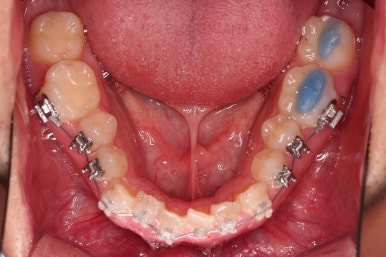

사용한 장치 : 자가결찰 세라믹(엠파워 클리어, Empower clear) + 미니스크류 + RPE(악궁확장장치)

확장 이 후 유지 기간동안 다른 치열을 가지런하게 해줍니다.

술전 교정 + 양악수술계획/협진 + 양악수술 이 삼박자가 잘 맞으면 술후교정은 일사천리로 진행됩니다.

큰 문제 없이 진행되고 좀 더 디테일을 맞추고 종료하게 됩니다.

당연히 교합/위아래 폭 등 치열이 좋아졌고요.